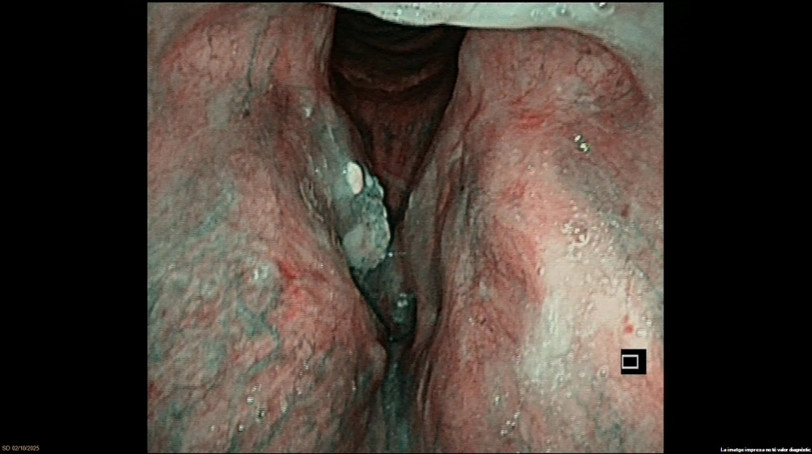

Exophytic lesion on the right vocal cord. NBI suspicious for malignancy. Laryngeal dysplasia. Ventricle and AC appear clear. Motility preserved